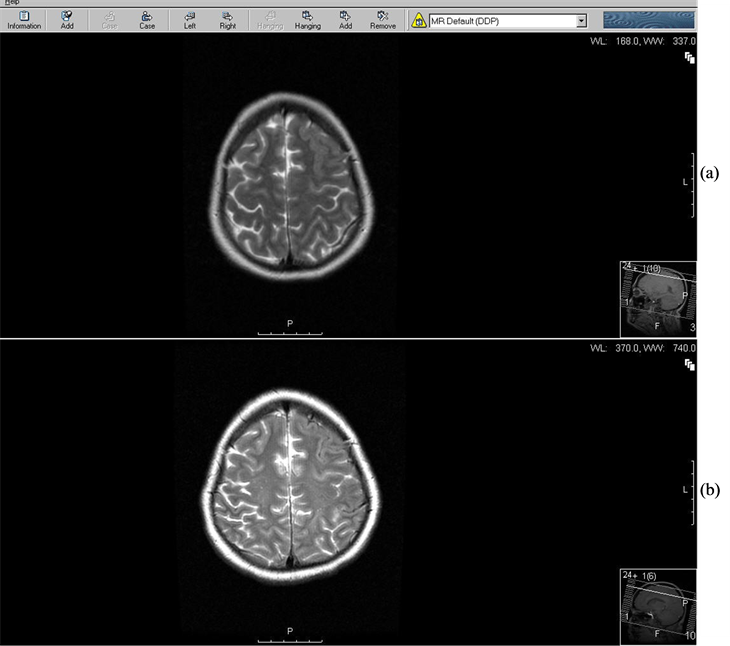

Figure 2.Brain MRI four days after cerebral revascularization is demonstrating vasogenic edema (VE) in the left frontal lobe (a). Five weeks later the edema has disappeared (b).

The symptoms of impaired visual acuity in our patient could have been attributed to vasogenic brain edema, which was demonstrated by MRI. Previous case reports described an association between reversible cortical blind- ness and vasogenic cerebral edema among patients with severe postpartum preeclampsia [6].